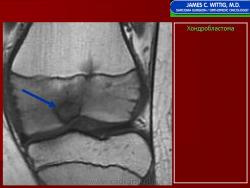

Хондробластома — это редкая доброкачественная опухоль, локализующаяся, главным образом, в эпифизе и отличающаяся своеобразным клеточным составом. Ткань новообразования представлена овальными, округлыми и веретеновидными клетками, напоминающими незрелые хондроциты (хондробласты). Зрелый гиалиновый хрящ определяется лишь в некоторых опухолях. Возраст больных варьирует. Мужчины поражаются в два раза чаше женщин. Пациенты предъявляют жалобы на боли в течение нескольких месяцев или лет, у некоторых больных определяются внутрисуставной выпот, припухлость и ограничение движений. Наиболее типичная локализация опухоли — проксимальные эпифизы плечевой и большеберцовой костей, а также дистальный эпифиз бедренной кости. У 20 % больных опухоль развивается в плоских или коротких трубчатых костях, преимущественно в пяточной и таранной. Изредка поражаются кости лицевого черепа, в том числе височная. В большинстве случаев новообразование выходит за пределы эпифиза и распространяется на метафиз. На фоне остеолиза обнаруживаются рассеянные участки обызвествления в виде пунктирных линий, а также разреженный трабекулярный рисунок. Хондробластома, как правило, не выходит за пределы кости, но изредка проникает в полость сустава. В процессе роста опухоли иногда возникает вторичная аневризматическая костная киста.

Рентгенологически хондробластома представляет собой сравнительно большой (2-4 см) очаг округлой формы, четко отграниченный от окружающей кости склеротической каймой. На фоне очага в большинстве случаев, но не обязательно определяются плотные включения, напоминающие хлопья ваты.

Рентгенологическая картина. Хондробластома выглядит как небольшой, от 3 до 6 см литический очаг, центрально или эксцентрично расположенный, с четкими контурами, занимающий около половины площади эпифизарной зоны. Хондробластома плоских костей и мелких трубчатых костей больших размеров, может сопровождаться припухлостью мягких тканей, вздутием кости и периостальной реакцией. Распространение процесса на метафизарную зону встречается часто.